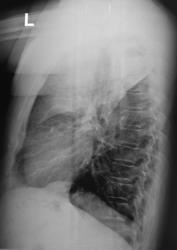

Контроль после флюорографии.  Жалоб нет!

Томограммы.

Возраст и предыдущая ФЛГ? А пока что саркома.

Спасибо! Пока останусь при своем мнении, такое поражение без клиники и без явного уменьшения объёма - саркома.

А объём, что сильно уменьшен, так по боковой, вроде бы и нет.

Саркома - потому что я не знаю иной патологии, такого размера поражения и без объёмного уменьшения. Тем более при отсутствии клиники: пневмония отпадает, остается саркома. Может, кто-то еще что предложит.

Жалоб нет или больной диссимулирует-всё одно. Ателектаз есть, нижнедолевой бронх сужен из вне,ФТБС-покажет, Нам остается только гадать.....

Ателектаз,а вот мне интересно почему верхушка воздушна или это  распад ?

Это не распад...А клапанные вздутия периферической ткани легкого-результат нарастающей обтурации бронха.